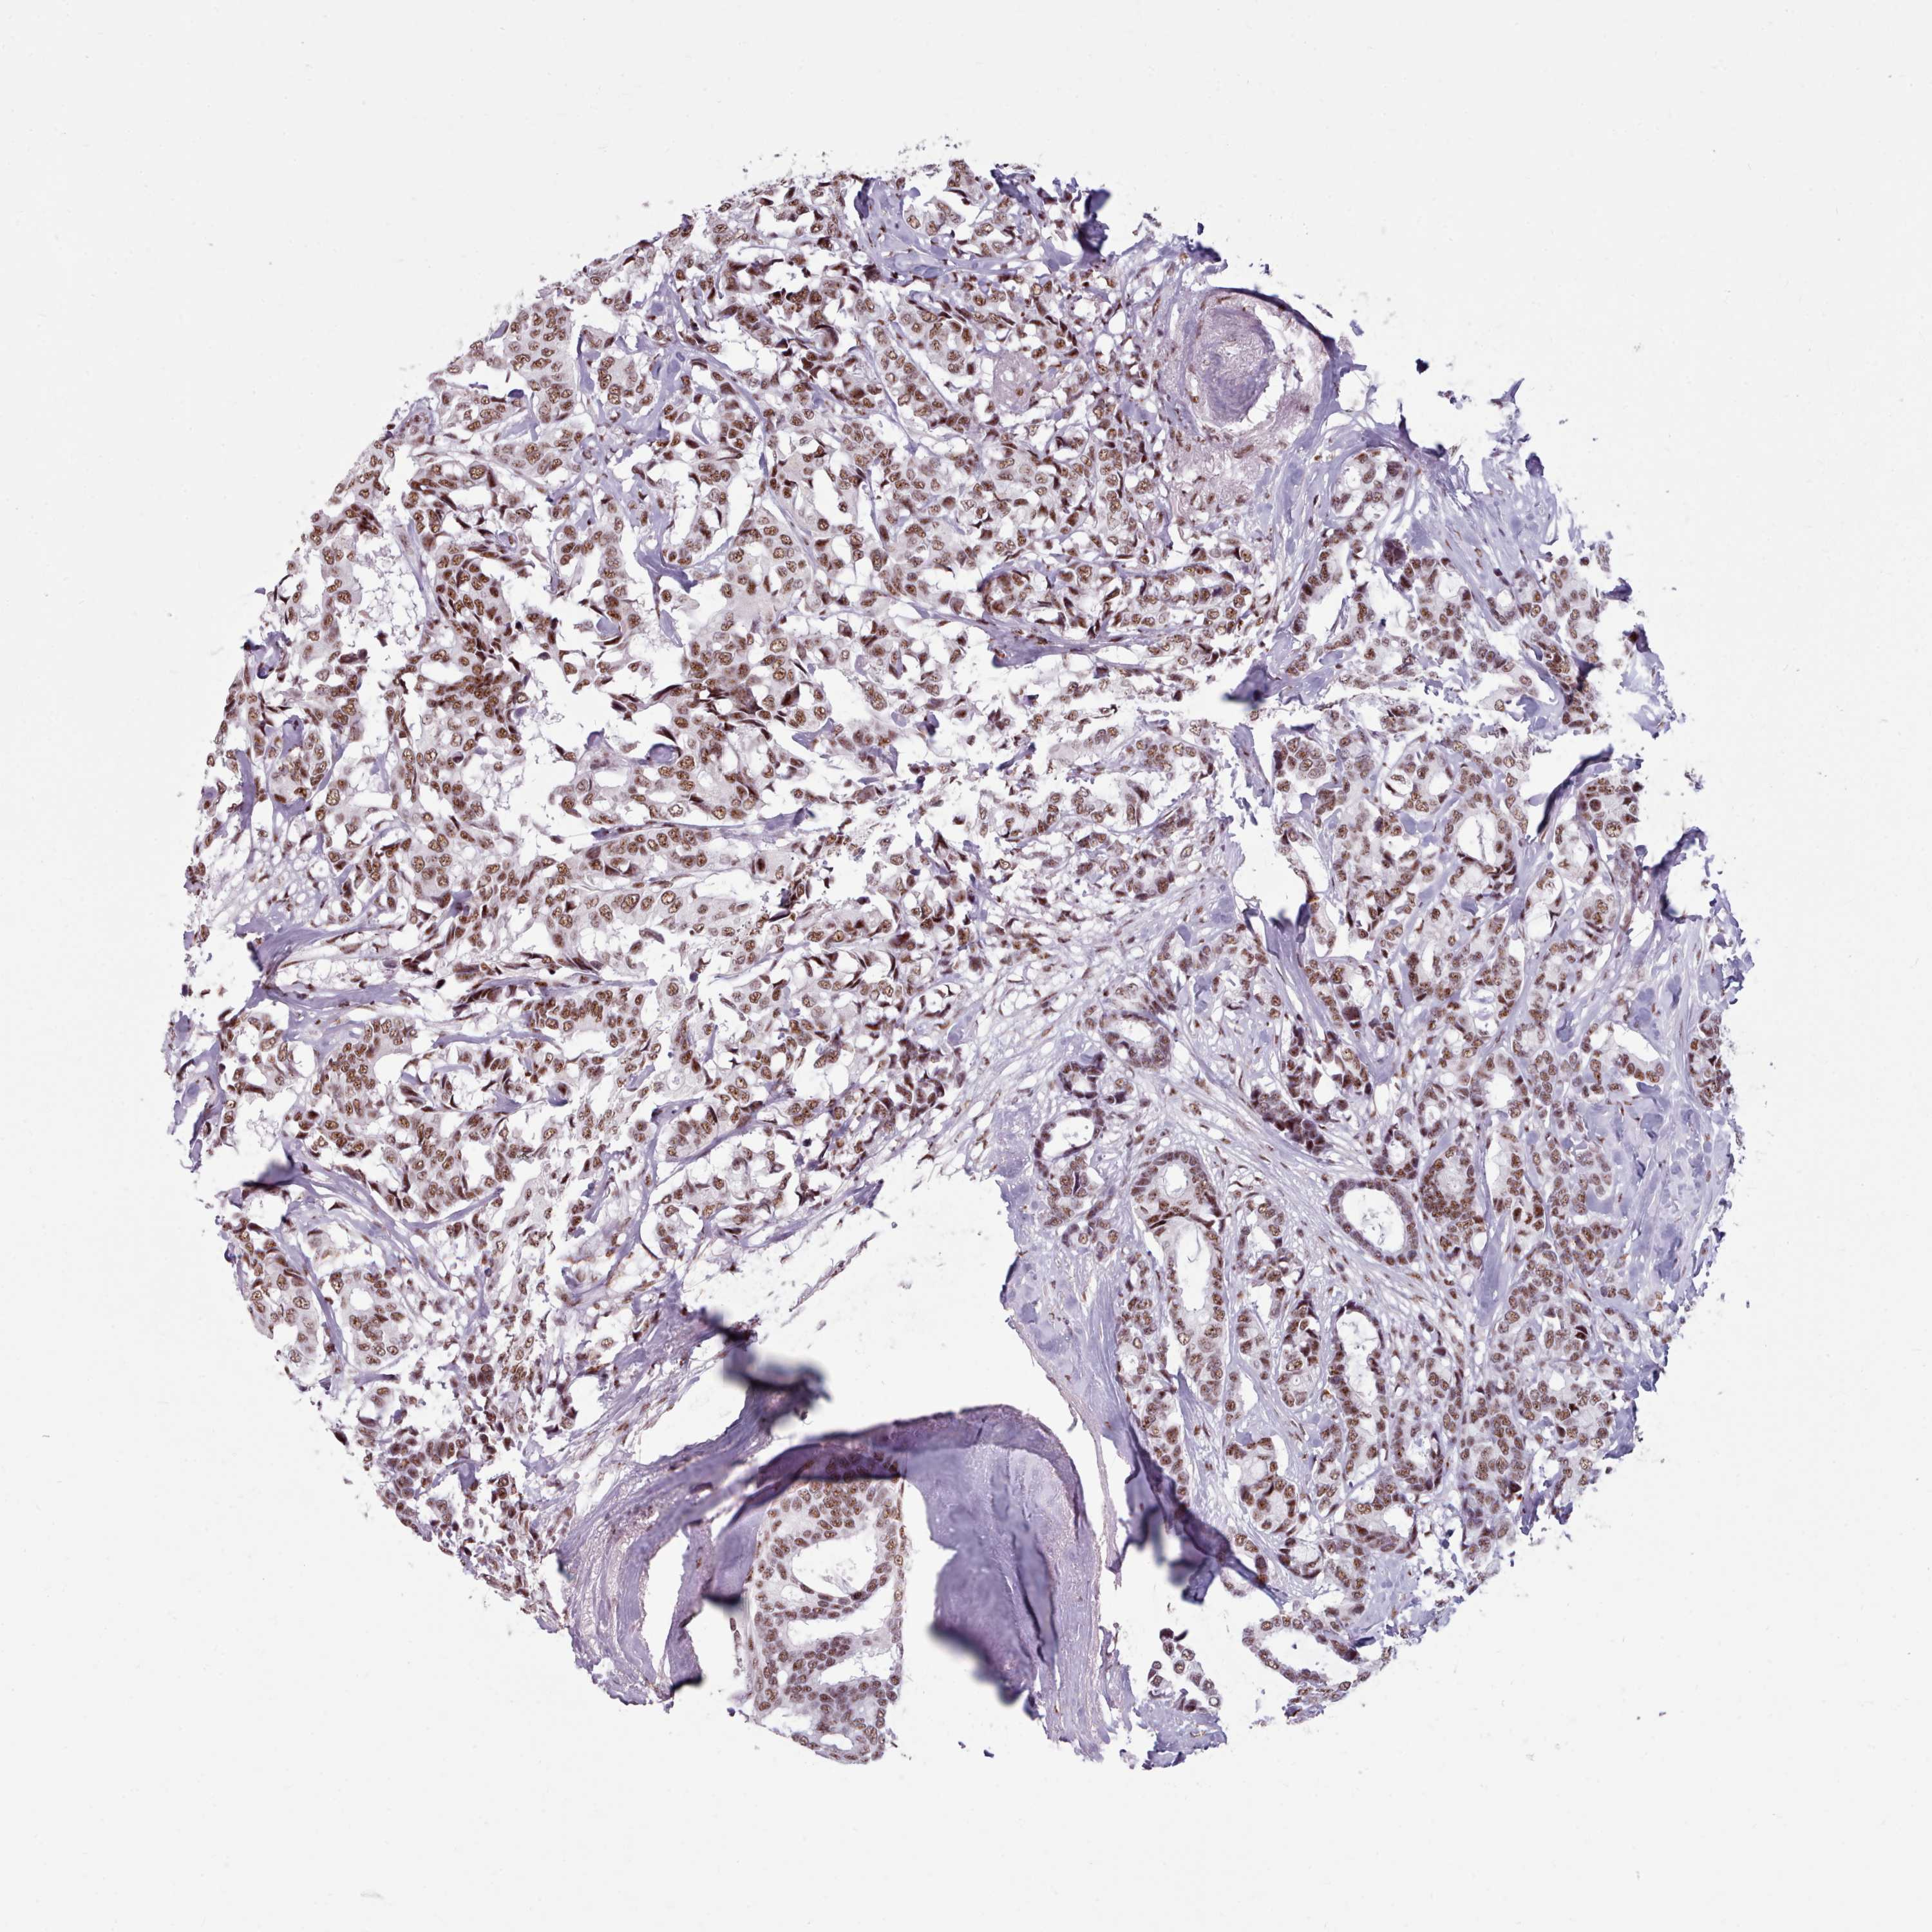

CANCER BREAST CANCER Show tissue menu

BRCA TCGA BRCA VALIDATION PROTEIN EXPRESSION